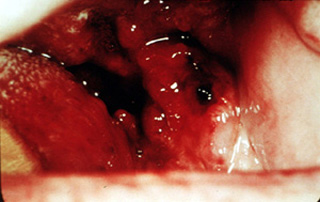

Este tumor necrótico fungoide de la lengua no ofrece ningún problema

para el diagnóstico. Desgraciadamente, éste no es el tipo de lesión que puede curarse prontamente y no representa una situación dónde

el odontólogo pueda realizar un diagnóstico temprano. |

Lengua

Esta lesión grande de la lengua tiene todos los rasgos clásicos de malignidad. Se

ulcera y vuelve acicatrizar.

El diagnóstico aquí es ciertamente fácil. |